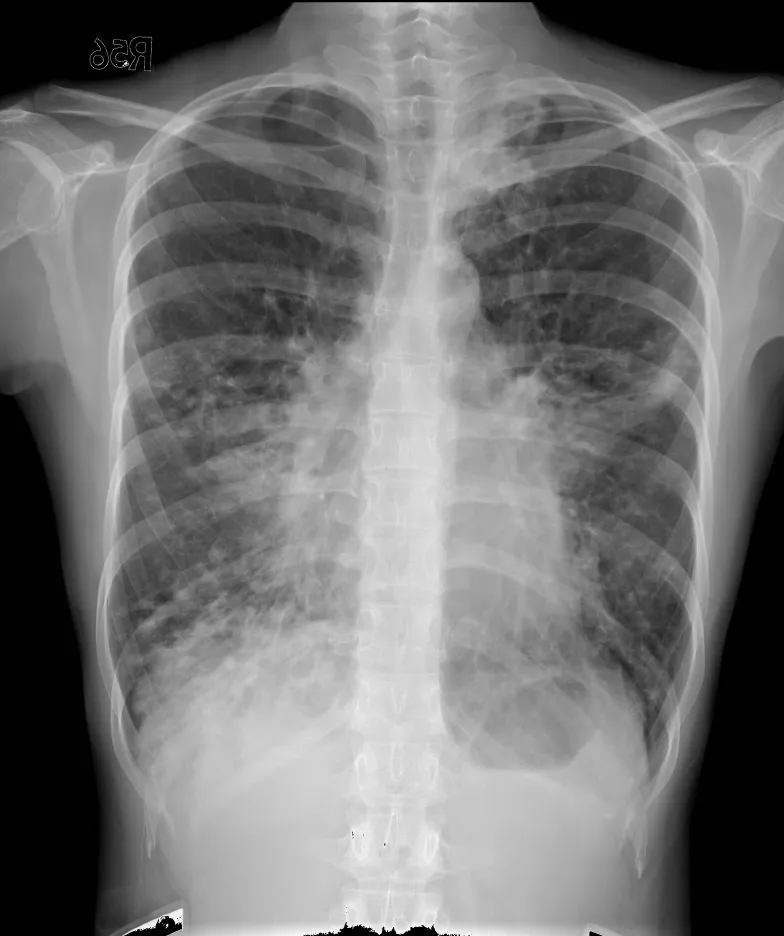

破題關鍵

這張胸部X光片顯示兩側肺部廣泛性的網狀結節狀浸潤,搭配病患長期咳嗽和體重減輕的症狀,強烈暗示惡性腫瘤的可能性,尤其是肺癌的瀰漫性表現或淋巴管癌病變。

選項拆解